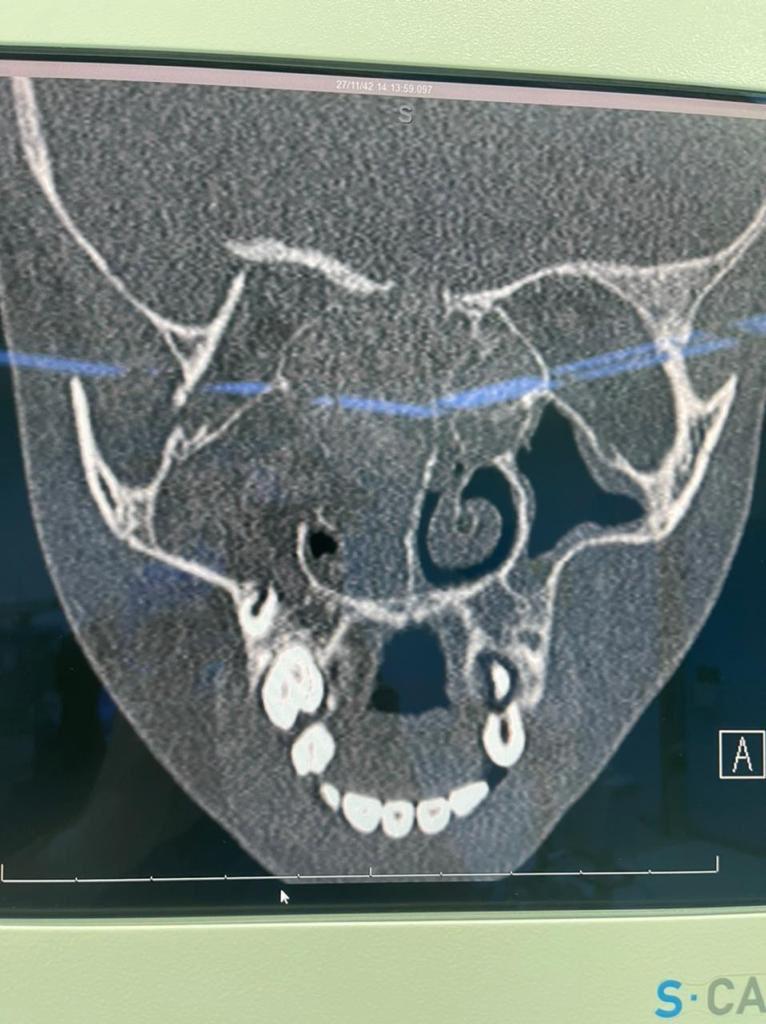

حيث حضرت للمستشفى و هي تعاني من إنسداد شديد في الأنف و صداع و بروز في منطقة العين اليمنى ، و بعد إجراء الأشعة و جميع الفحوصات اللازمة و التي أظهرت وجود لحميات و فطريات في الجيوب الانفية ، حيث كانت الفطريات ضاغطة على العين و قاع الجمجمة ، ما دعا الفريق الطبي إلى إجراء عملية جراحية عن طريق المنظار لتنظيف الجيوب